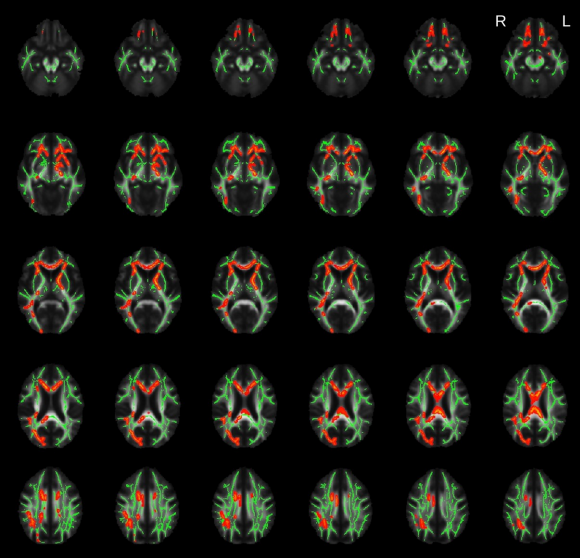

CSF和血浆中Nf-L的水平与额叶颞叶痴呆(FTD)等神经退行性疾病的变性有关,目前Nf-L被认为是FTD中最具潜力的诊断和预后生物标志物。尽管神经丝在健康神经系统中的位置和功能表明Nf-L升高与白质变性之间存在联系,但这种说法在体内尚未得到充分阐明。该研究通过将20名行为变异性FTD(bv FTD)患者的Nf-L血浆浓度与弥散张量成像(DTI)指标相关联,提供了Nf-L血浆水平与bvFTD患者白质变性之间具有关联性的证据。研究结果表明,血浆Nf-L浓度升高与广泛分布的白质束(包括上纵束,额枕束,前丘脑辐射和背扣带束)中的部分各向异性(FA)降低有关。血浆Nf-L浓度还与右侧内侧前额叶皮层和右侧外侧眶额叶皮层的一部分皮质变薄相关。上述结果支持以下假设:血液Nf-L水平反映了bvFTD中神经退行性疾病的整体水平,并有助于加深我们对FTD血液生物标志物与疾病过程之间相关性的理解。

图1. 基于体素的TBSS分析结果。红色簇表示bvFTD患者中部分各向异性(FA)和Nf-L水平之间呈负相关。平均骨架显示为绿色。

图2. 通过对上纵束(SLF)、额枕束(FOF)、丘脑前辐射(ATR)、背扣带束(dCin)、合束筋膜(UF)、扣带束的下/海马区部分(iCin)以及皮质脊髓束(CST)等多个区域的比较得知,在FOF,SLF,左UF和右dCin等区域,FA与血浆Nf-L水平之间呈显著负相关性。左ATR,右UF和左dCin中的FA值和Nf-L之间的相关性只有很小的显著性。在CST中未发现显著相关性。相对于健康对照组,bvFTD组中的FA显著降低(除下扣带束外)。